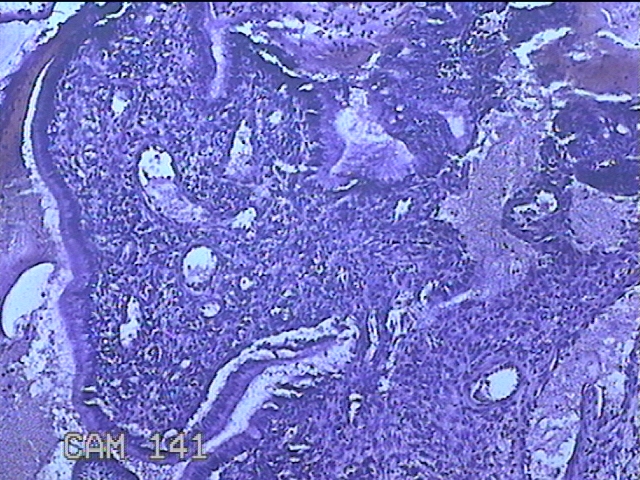

宫颈赘生物

性别

女

年龄

36岁

临床诊断

一般病史

发现宫颈赘生物1个月。

标本名称

大体所见

灰白暗红色肿物1x0.7x0.2cm一个,表面糜烂。

图4